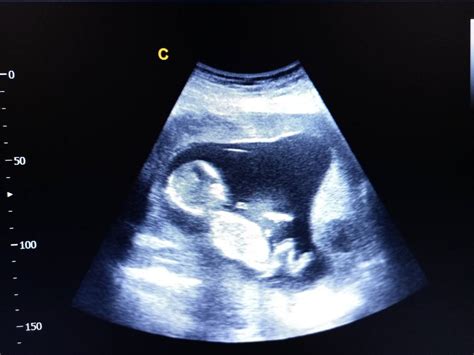

În săptămâna 32 de sarcină, corpul bebelușului este aproape complet format, iar organele sale funcționează din ce în ce mai eficient. Fătul măsoară aproximativ 41,6 centimetri de la creștet până la călcâie și este de mărimea unei verze kale. Aproximativ 97% dintre bebeluși se nasc cu capul în jos, poziționându-se astfel pentru naștere. Corpul bebelușului acumulează grăsime brună, esențială pentru termoreglare după naștere, și își antrenează reflexele, precum reflexul Moro și reflexul de supt.